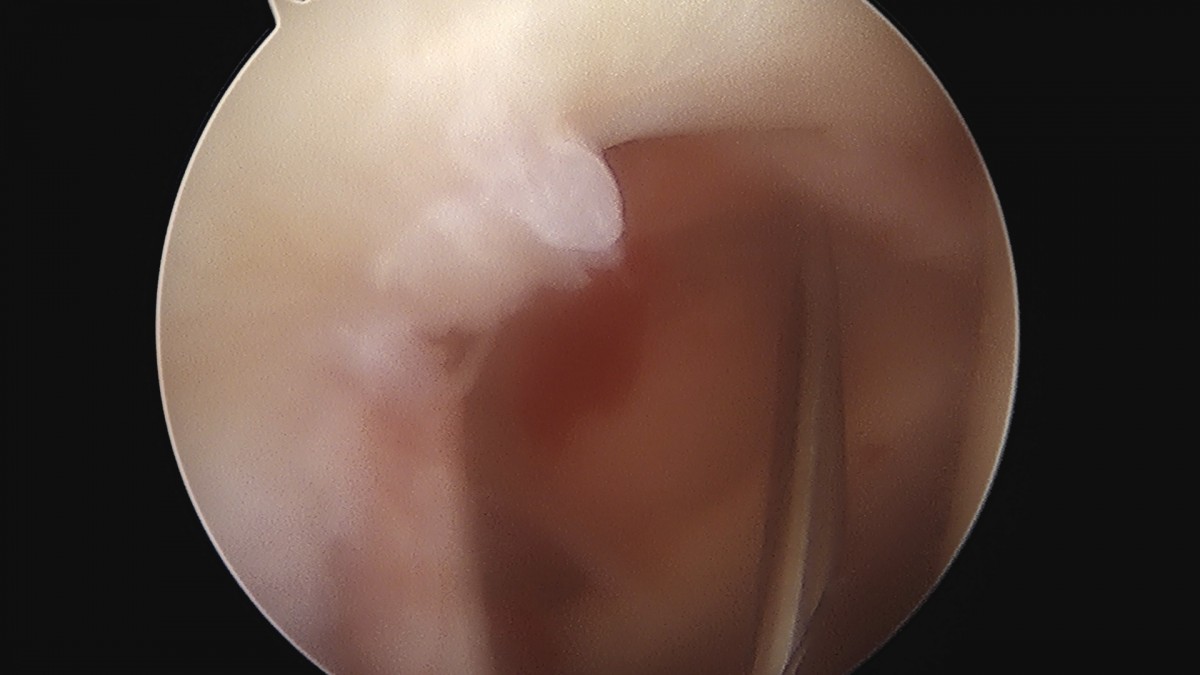

이재상원장님 어깨 견봉하 감압술 김선O 환자

dae765e4d9ac96aee867c9d6292d8784_1758004049_4756.jpg